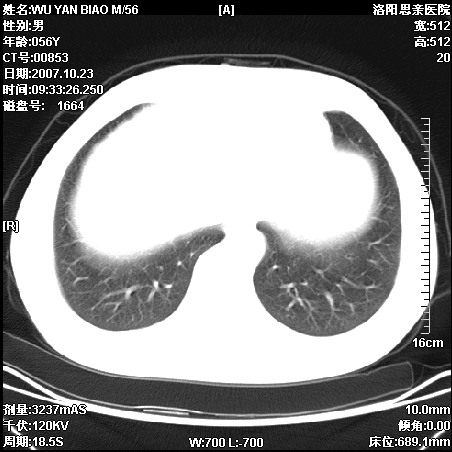

标题: CT10160:M56Y,体检发现,病人无不适,病人随访中 [打印本页]

标题: CT10160:M56Y,体检发现,病人无不适,病人随访中

后上纵隔占位,与肺交界清,宽基底附着脊柱,密度均匀,局部骨质无明确改变.

考虑;神经源性肿瘤,---起源交感n链?,不除外肠源性囊肿.

1、病灶在后纵隔脊柱旁沟内,此处是神经原性肿瘤的好发部位

2、病灶边缘光滑整齐,更说明病灶来于纵隔,由于有胸膜的包裹所以才导致这么光滑的边缘

3、病灶内的密度均匀